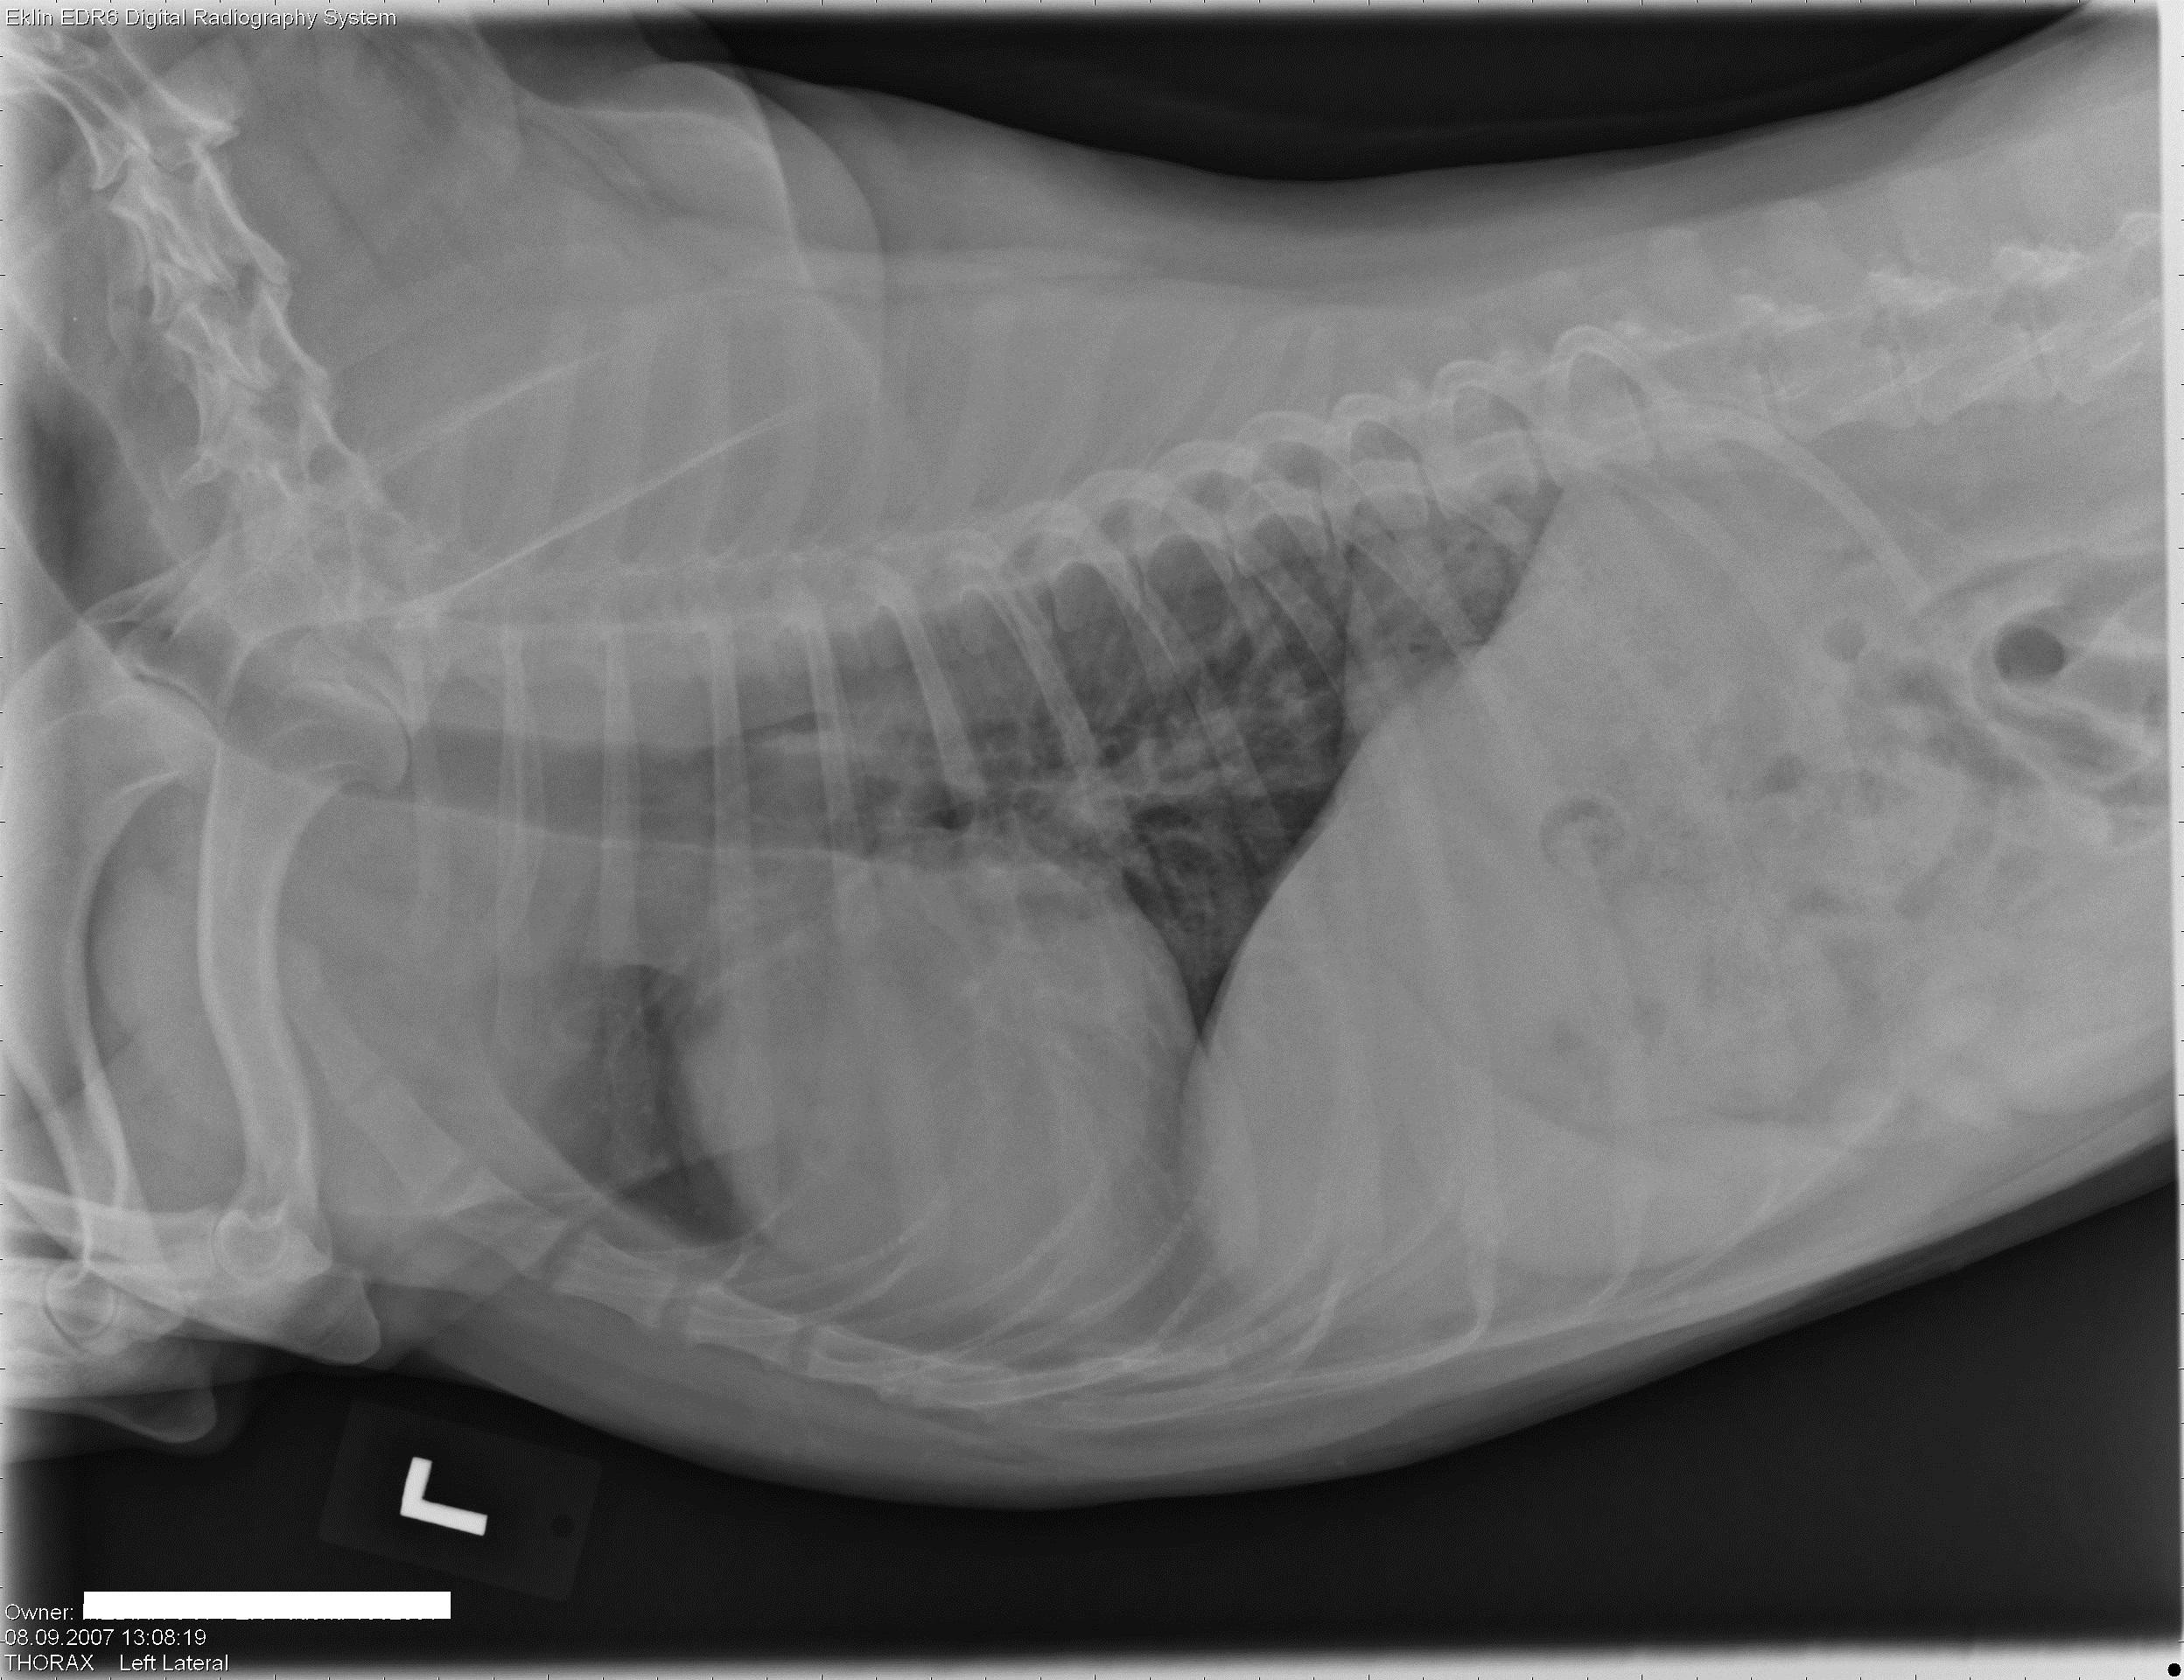

Een 10 jaar oude, mannelijk, gecastreerde hond wordt bij je aangeboden met erge tenesmus.Â

Hieronder vind je 5 Röntgen foto’s thorax en abdomen. Gebruik de pijltjes om erdoor te schuiven, of klik op de foto om te vergroten.